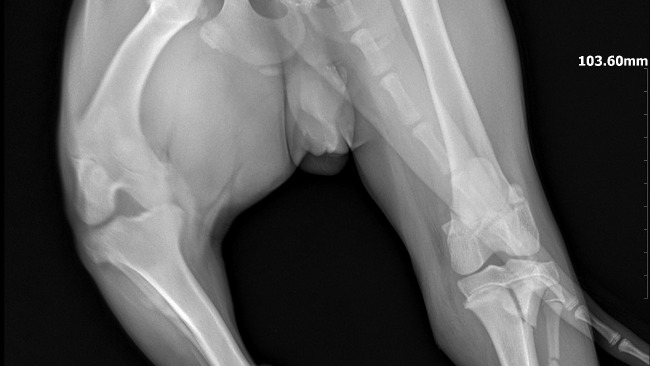

Harry to młodziutki (ok.1 roku) wyżełek po wypadku komunikacyjnym, w którym ucierpiały jego łapki. Łapka przednia wymaga natychmiastowej interwencji chirurgicznej!!!

Dołączam zdjęcia rtg łapek, które ucierpiały oraz opis z lecznicy.